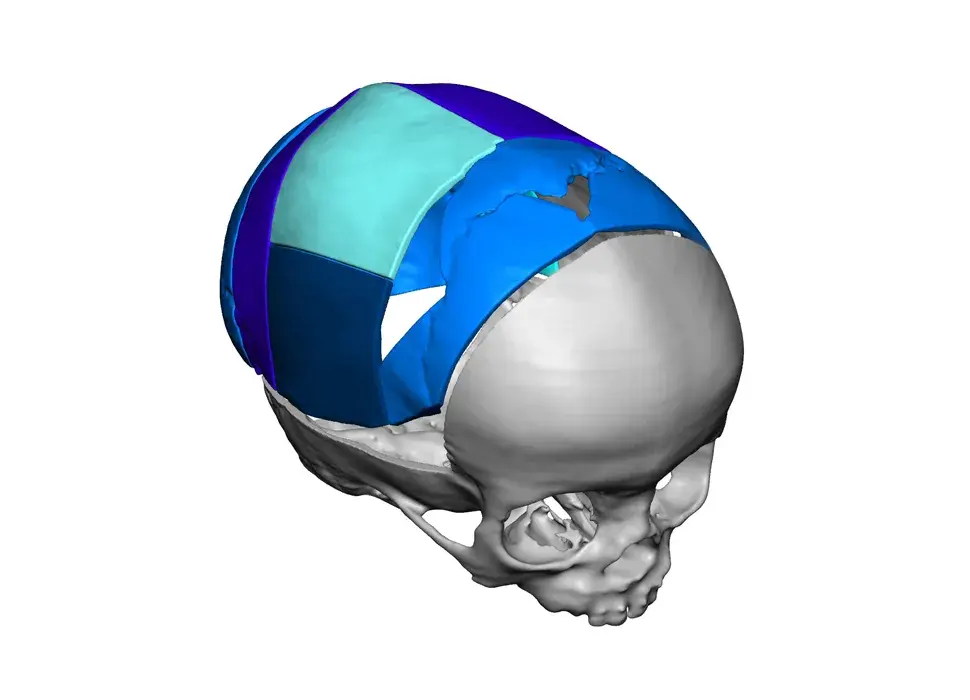

3D Systems' VSP® surgical planning solutions for craniomaxillofacial (CMF) applications received FDA clearance as a service-based approach to personalized surgery over 10 years ago.

3D Systems and Stryker Corporation have partnered to provide surgeons with best-in-class products and services for craniomaxillofacial surgeries. As a leader in personalized healthcare solutions, 3D Systems has planned and delivered devices for more than 140,000 patient-specific cases. The Stryker Craniomaxillofacial business specializes in providing patient-specific options and innovative solutions that help drive efficiencies in surgical suites. The combination of Stryker’s specialized team and advanced implants with 3D Systems' cutting-edge 3D printing technologies and expert consulting services positions both companies to provide a superior level of service to healthcare professionals who use these revolutionary solutions.